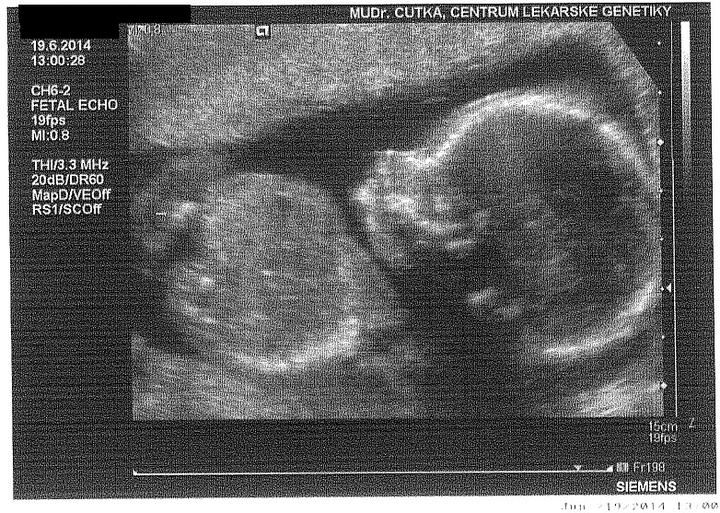

Tak dnešní screening dopadl na 1*... Všechno naprosto dokonalé, miminko zdravé, testy i UZ v pořádku. Mimčo měří 6 cm. Bylo krásně natočené a mávalo nám ručičkama. Paní doktorka nám vše krásně vysvětlila a ukázala... Manžel byl nadšený a je pyšný, protože budeme mít na 80% holčičku 🙂 Jsme nesmírně šťastní 🙂